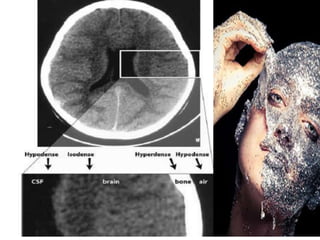

B is for Blood

• Blood becomes hypodense

at approximately 2 weeks.

•Blood becomes

isodense at

approximately 1 week.

• Acute blood is bright white

on CT (once it clots).

• Blood becomes

hypodense at

approximately 2 weeks.